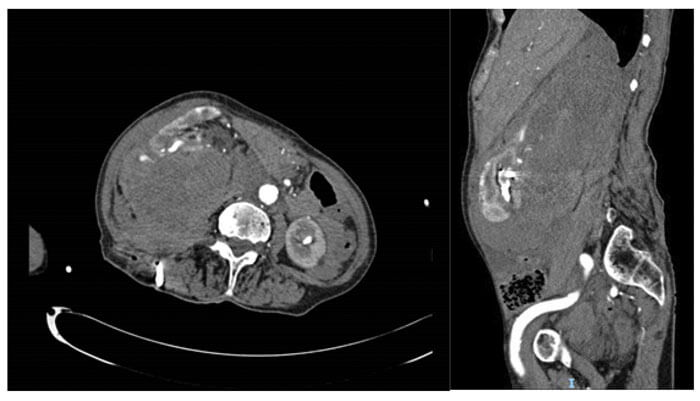

Figure 2: Post-PCNL bleed into retroperitoneum.

Postoperative bleeding (Figure 2) can be usually resolved by a short period of nephrostomy clamping (10-15 minutes), especially if arising from venous vasculature. However, it is prudent to have a high clinical incidence of suspicion in such cases and proceed to renal angiography with angioembolisation. The postoperative transfusion rate varies widely in the literature, with the British Association of Urological Surgeons quoting the national average as 2.1% [29].

Whilst initially it might be reassuring, the absence of any blood-stained urine in the urethral catheter may indicate ipsilateral ureteric obstruction (either from a stone fragment, ureteric oedema or a blood clot) as the clear urine seen in the bladder represents normal urine from the contralateral kidney. Within this scenario, persistent and worsening haematuria through the nephrostomy is an indicator of clot-colic, for which additional vigilance for bleeding is needed. In any of these situations, imaging (by CT KUB, nephrostogram or CT angiogram as appropriate) will identify the level and cause of obstruction and allow onward management as required, including the opportunity to deploy an antegrade stent via the nephrostomy tract (Figure 3).

Figure 3: Pain on clamping nephrostomy with ensuing extravasation secondary

to distal obstruction followed by interval nephrostogram after antegrade stent.